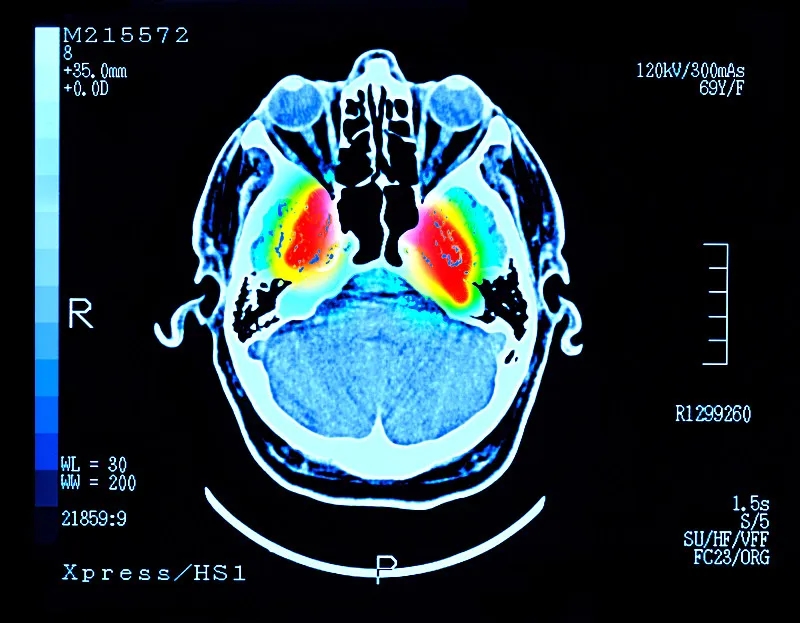

帕金森病 (PD) 是大腦中的一種疾病,它會殺死產(chǎn)生一種叫做“多巴胺”的化學(xué)物質(zhì)的神經(jīng)元。多巴胺是一種重要的化學(xué)物質(zhì),負責(zé)大腦內(nèi)神經(jīng)元之間的交流。細胞死亡主要發(fā)生在“黑質(zhì)”,這是大腦中主要的多巴胺產(chǎn)生區(qū)域。

這些治療可緩解帕金森病的癥狀,但不會減緩或逆轉(zhuǎn)大腦神經(jīng)細胞的損傷。隨著時間的推移,盡管進行了治療,但臨床特征會變得更糟。當患者被診斷出患有帕金森癥時,他們通常已經(jīng)患病多年,并且黑質(zhì)內(nèi)的多巴胺細胞已經(jīng)丟失了一半以上。早期檢測帕金森癥的測試可能有所幫助,但科學(xué)家們正在尋找一種方法來替換受損的細胞。